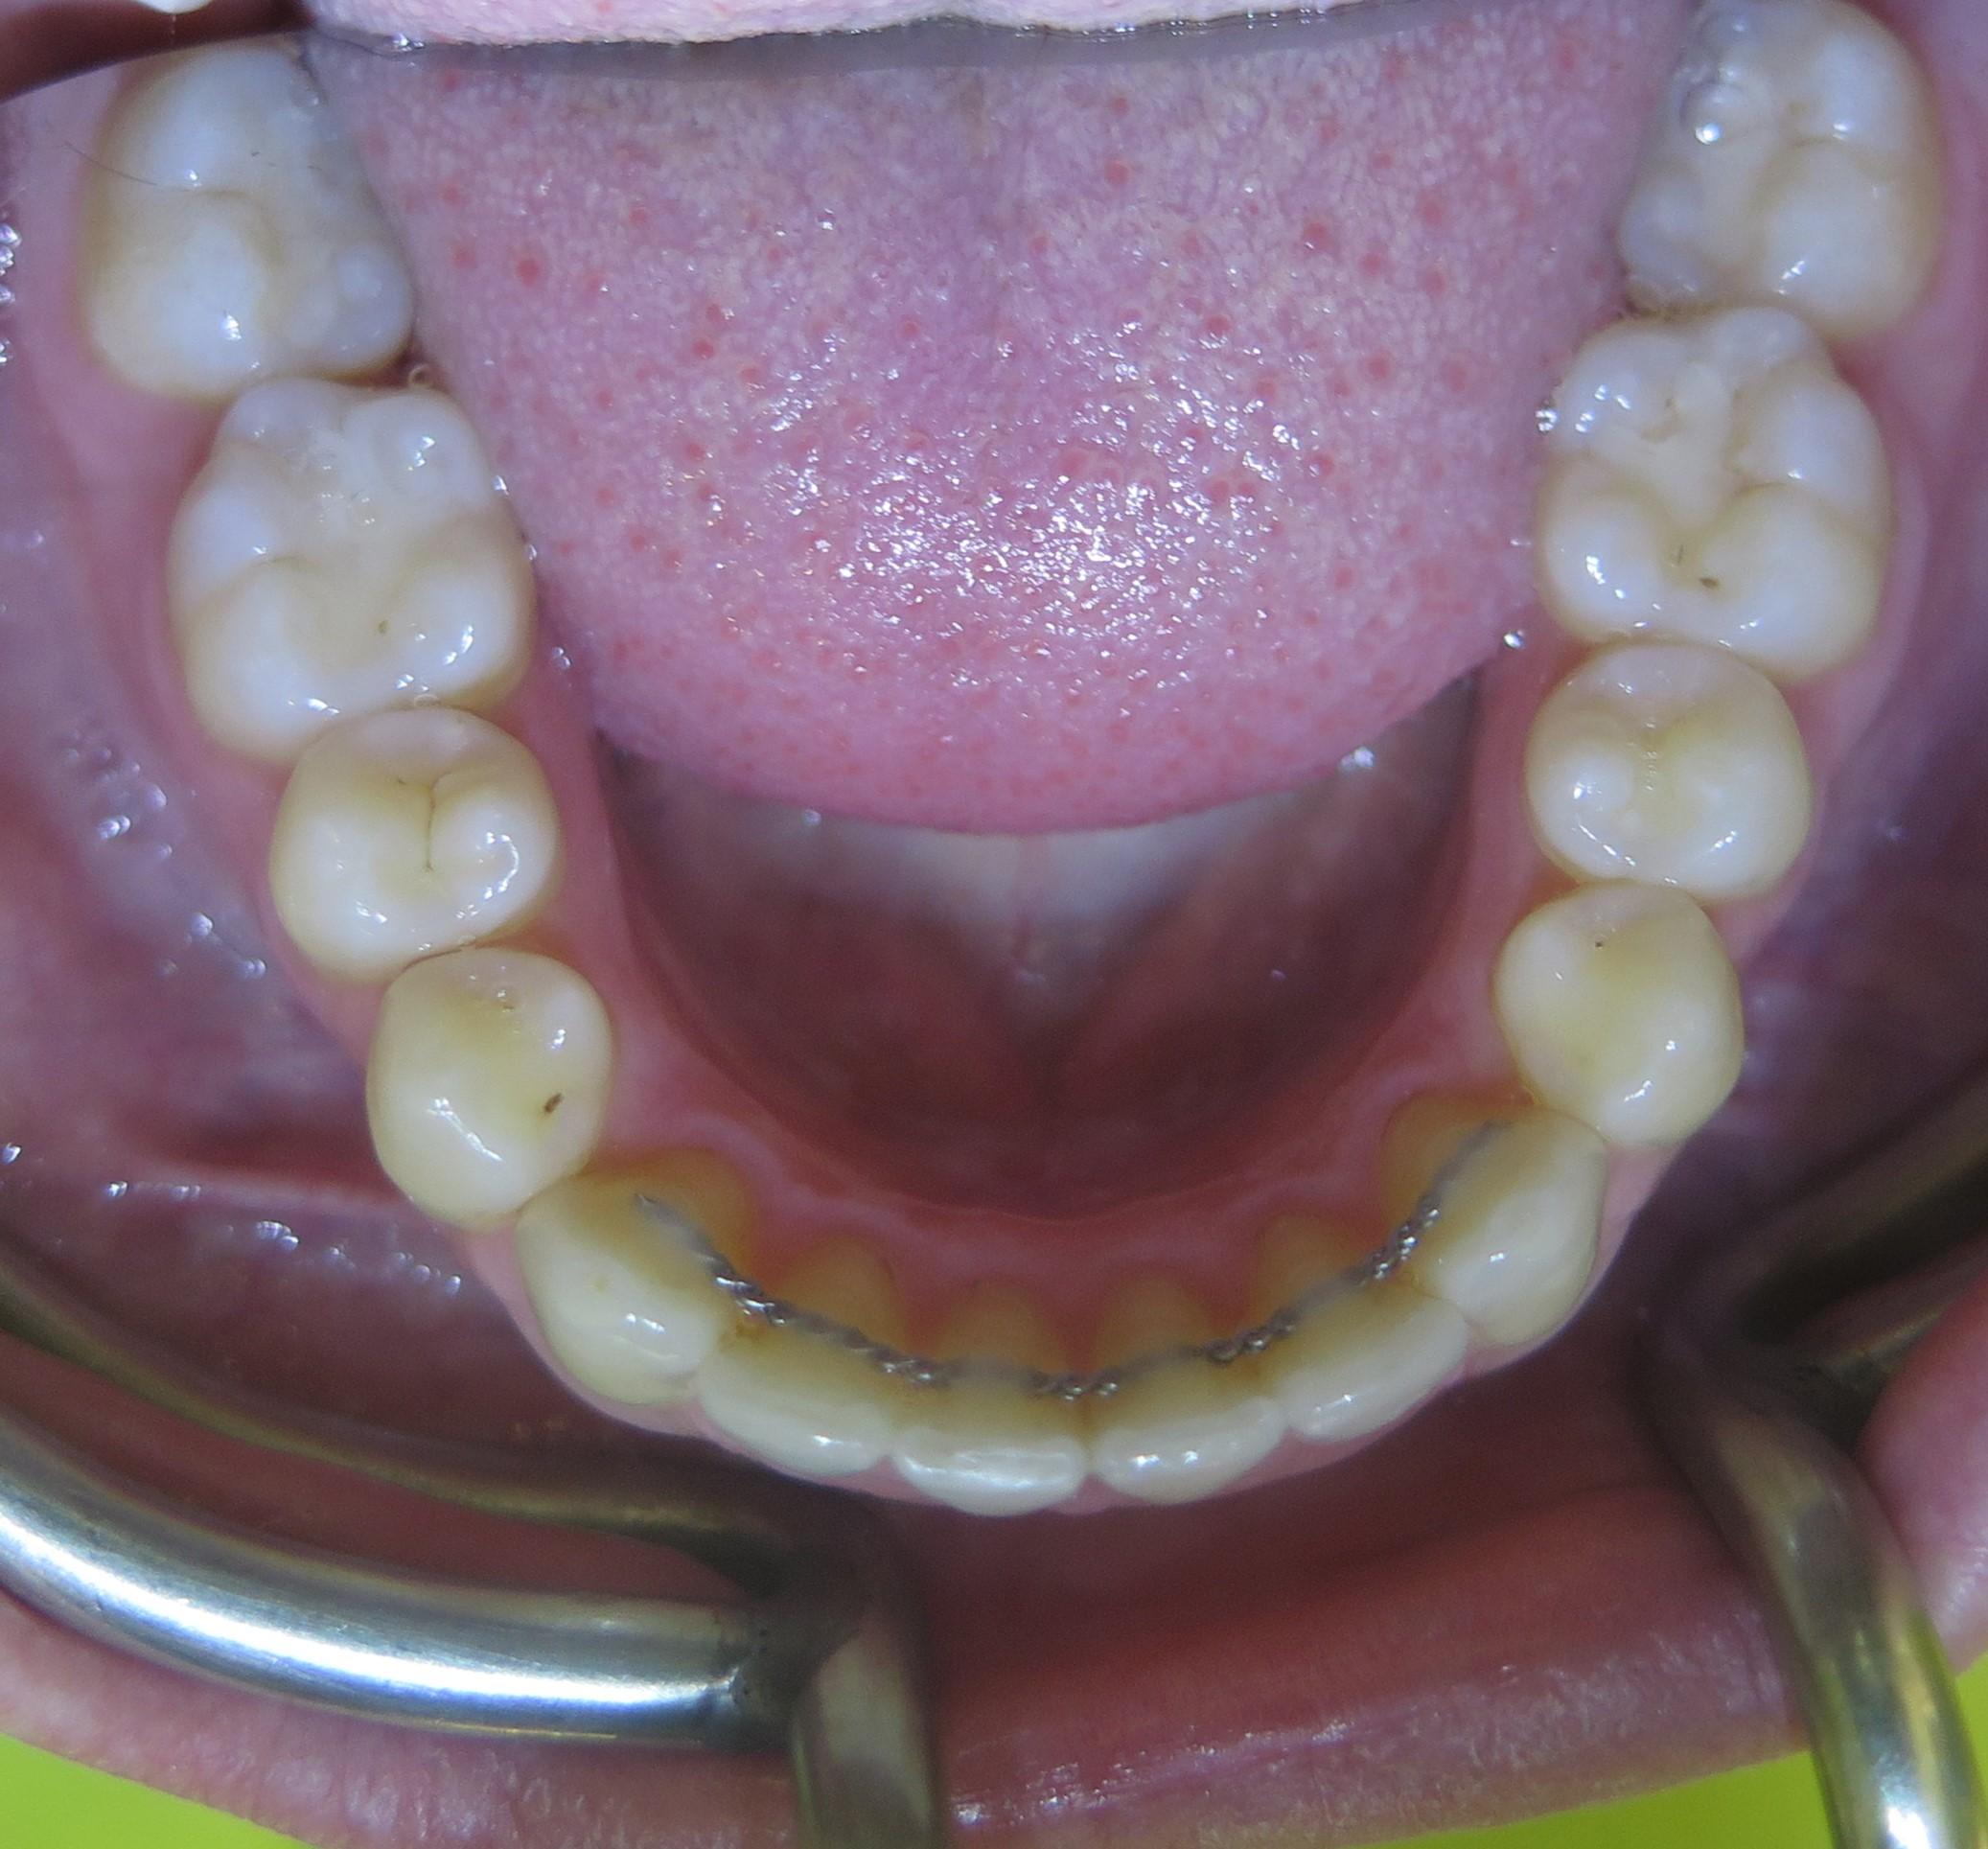

Pacjentka zgłosiła się do Kliniki Platinum z powodu niezadowalającego kształtu i koloru zębów oraz występowania licznych recesji dziąsłowych w żuchwie.

Dzięki precyzyjnej diagnostyce, doktor Magdalena Zawirska opracowała kompleksowy plan leczenia, który obejmował: stomatologię zachowawczą, periodontologię i protetykę stomatologiczną. Zastosowano licówki i korony pełnoceramiczne, przeprowadzając kompleksową rekonstrukcję zwarcia.

Pacjentka może się teraz cieszyć się pięknym i zdrowym uśmiechem